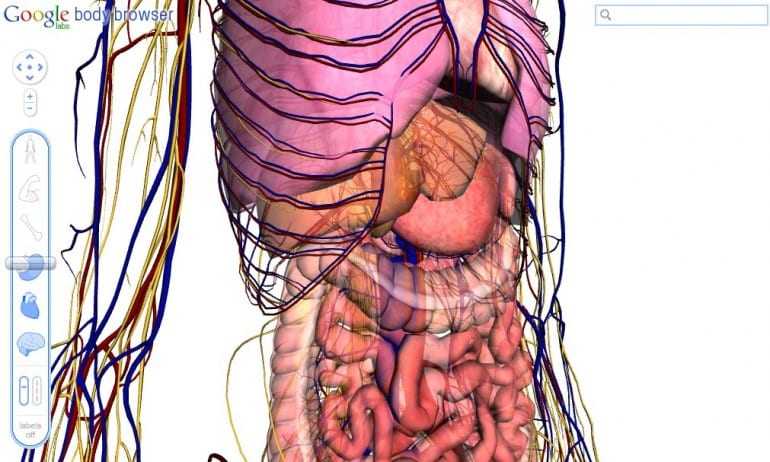

Αν και ακόμη σε πειραματικό στάδιο το Body Browser επιτρέπει σε χρήστες να ‘τεμαχίζουν’ το ανθρώπινο σώμα μέσα από τις στρώσεις του σώματος σε ένα τρισδιάστατο μοντέλο. Με χρήση εικονικών ‘μαχαιριών’ γίνεται εύκολα η εξερεύνηση των οργάνων που μας κάνουν να… λειτουργούμε.

Στήθηκε για να είναι και μια επίδειξη της τεχνολογίας WebGL, επιτρέπει σε έναν browser να σχηματίζει 3D γραφικά χωρίς να υπάρχει ανάγκη για plugins. Το Body Browser για την ώρα είναι δουλειά που στήνεται στα Google Labs και όποιος έχει έναν WebGL-enabled browser – όπως οι τελευταίες εκδόσεις των Chrome και Firefox για Windows και ο Safari για Mac – θα πρέπει να μπορούνε να ‘εισέλθουν’ σε πολλαπλές στρώσεις, να κάνουν zoom in και out, και να αναζητούν συγκεκριμένα μέρη του σώματος όπως κάνουμε για τις πόλεις του Google Maps.

Είναι μια εντυπωσιακή επίδειξη της HTML5 και WebGL τεχνολογίας και πραγματικά θα δούμε πολλά ωραία με αυτή αφού έτσι δεν χρειάζεται να χρησιμοποιούνται δυνατές κάρτες γραφικών.